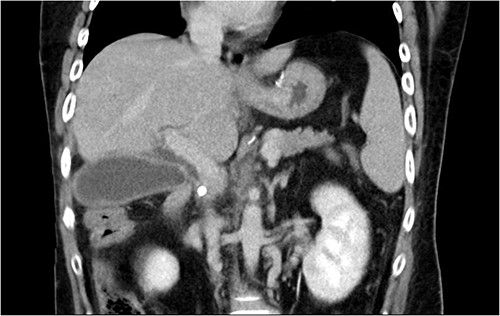

Initial laboratory findings revealed significant hyperbilirubinemia, liver enzyme elevation and mild PT prolongation. Abdominal computed tomography showed a CBD stone caused obstruction, resulting in upstream biliary dilatation and acute cholecystitis (Fig. 1). Besides, small caliber of inferior vena cava, splenic vein, and right iliac veins with thrombosis and prominent collaterals formation was also shown on the image.

Abdominal CT revealed CBD stone resulting in upstream biliary dilatation and acute cholecystitis.